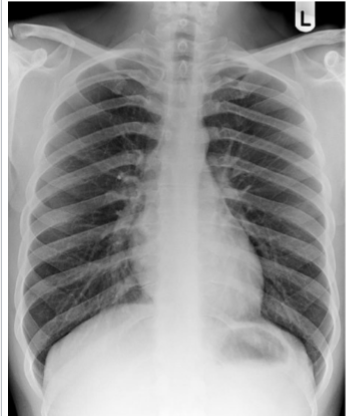

Identify cardiophrenic angle, R + L hemidiaphragms, stomach bubble, liver, spleen

yes

identify hemi diagrams (2) and stomach bubble